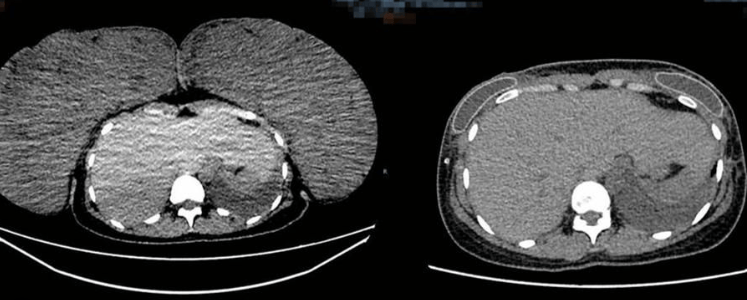

帕米莉亚患上的“巨乳症”是相当罕见的疾病,根据可查阅的数据显示,截止2008年,被记录的案例仅有115例。

这种疾病会导致乳房组织异常快速生长,研究者认为该疾病可能具有很强的遗传倾向,多发于青春期或者是怀孕期间,这时候是激素发生剧烈变化的时期。最可能的原因被认为是激素失衡导致的,乳房组织对正常的雌激素和孕激素异常敏感,使得腺体和脂肪过度增生。

但具体原因还未知,毕竟案例太少,很难系统化进行研究。

还有可能是其他问题引发的,比如病理性肥胖导致的脂肪堆积、或者是一些含激素的药物或部分精神类药物产生的副作用、还有可能是例如肢端肥大症的全身性疾病导致的。

长久下来,这绝对不是什么好事情,会给患者带来大量的困扰。心理上她们会因为他人的凝视和骚扰而产生巨大压力,感到焦虑和自卑,生活和社交的品质都受到严重影响。身体上则会有严重的负担,导致慢性的颈肩背疼痛、呼吸困难,压迫神经导致手臂麻木、脊柱变形,乳房下皮肤还可能因长期摩擦潮湿而出现皮炎、感染甚至溃烂!

我在搜索资料的时候,就在研究论文中看到了非常触目惊心的图片,已经感染得扩散到其他部位了,非常的可怕。

就目前来说,最有效的解决方法还是进行乳房缩小手术,以此去移除多余的腺体和脂肪组织,这样肯定是立竿见影的,但问题是这种手术太贵了!不是谁都能负担得起的。

2022年,BBC就曾报道有一个英国女子做了这个手术,她花费了13360美元,最难受的是后面还复发了。